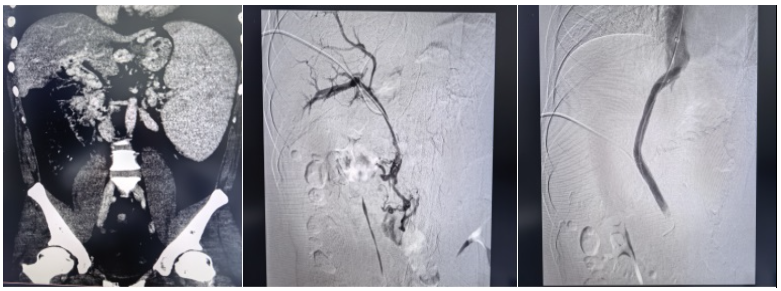

此次手术被业内视为介入领域的“极限挑战”,核心难点在于患者极为罕见的血管条件:门静脉主干完全闭塞,门脉海绵样变,脾静脉与肠系膜上静脉广泛血栓充填,常规TIPS手术缺乏有效流入道,标准穿刺路径完全失效。在血管解剖结构破坏、解剖标志模糊、血栓弥漫充填的极端条件下,从零构建肝内分流通道,对术者的操作精度、临床经验与应急处置能力均提出极高要求。

“没有通道,我们就为生命开辟一条通道。”面对患者与家属的殷切期盼,梁琪带领吴作为、骆雷等核心团队成员毅然迎难而上。术前,团队反复研读影像学资料,全面评估血管条件与手术风险,制定了周密的个体化手术方案。术中,团队凭借深厚的介入诊疗功底,沉着操控、精准穿刺,在闭塞多年的血管中耐心探查、精细开通,成功将支架置入门静脉主干并建立肝内分流道,显著降低门静脉压力,从根源上解除致命大出血风险,实现微创、安全、高效救治,疗效远超家属预期。